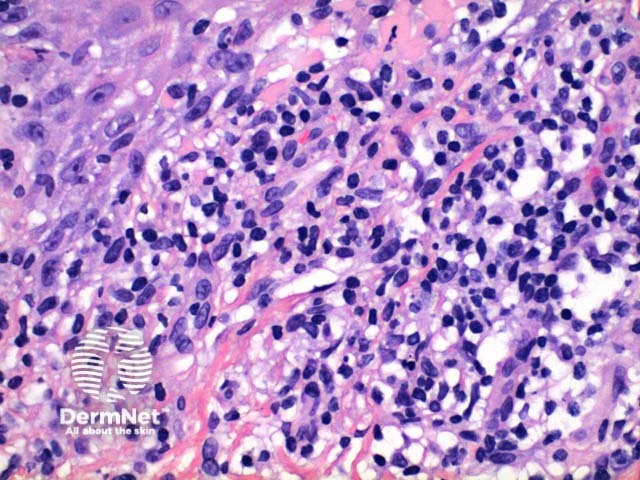

Scanning power view of lichen planus shows a lichenoid reaction pattern (Figure 1) characterised by the combination of degeneration of the basal layer of the epidermis and a band like lymphocytic infiltrate obscuring the dermoepidermal junction. There is irregular epidermal hyperplasia forming a characteristic saw-tooth appearance with wedge-shaped hypergranulosis (Figures 1 and 2). The basal layer of the epidermis exhibits vacuolar degeneration with typically prominent necrosis of individual keratinocytes (Figure 3). The inflammatory infiltrate is chiefly lymphocytic and forms a dense band in the superficial dermis (Figure 4).

Figure 3